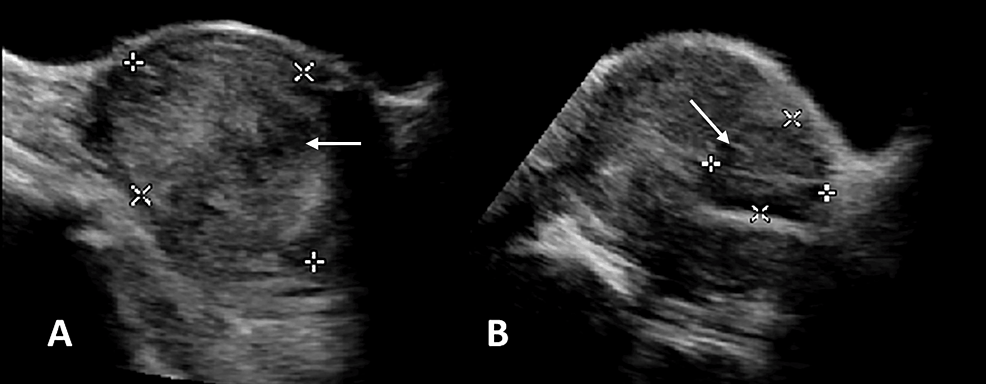

Large Cervical Leiomyoma of the Uterus: A Rare Cause of Chronic Pelvic Pain Associated With Obstructive Uropathy and Renal Dysfunction: A Case Report

Large cervical leiomyomas (≥10cm) are extremely rare. Our case report concerns the surgical treatment of a patient with a large cervical leiomyoma associated with chronic pelvic pain, bilateral hydroureteronephrosis and...

Conclusion: Large leiomyomas of the cervix are extremely uncommon, and their treatment with main laparotomy or laparoscopy surgery presents several difficulties and challenges. Chronic obstructive uropathy secondary to large cervical leiomyoma can result in renal dysfunction with a significantly increased risk of morbidity and mortality....